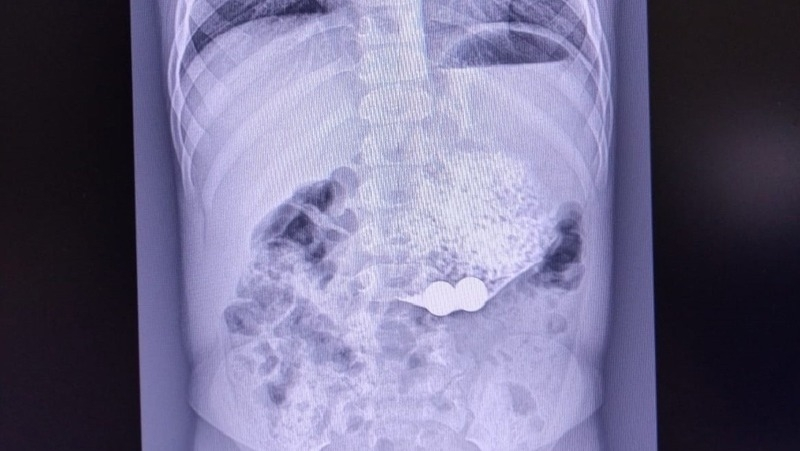

Третьего малыша пришлось прооперировать. У него наблюдалась многократная рвота, и родители обратились к врачу по месту жительства. Медики выяснили, что в тонком кишечнике ребёнка находятся инородные тела — магниты.

Пациента отправили в детскую крайбольницу, где экстренно прооперировали. Во время хирургического вмешательства врачи выявили кишечную непроходимость из-за сращения кишечных петель — они притягивались друг к другу магнитами. Операция прошла успешно, ребёнок продолжает проходить лечение.